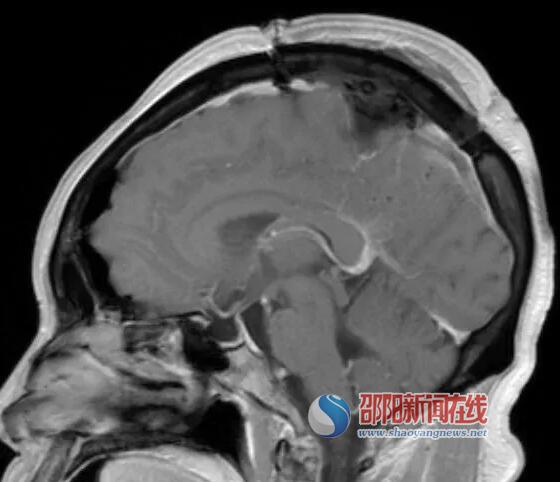

12月4日,神经外科对李阿姨实施了显微镜下颅内肿瘤simpsonI级切除。经过8个多小时紧张的手术,成功完整地将肿瘤切除。

(术后复查,出院时,李阿姨的四肢肌力V级,无肢体麻木,可胜任正常工作生活)